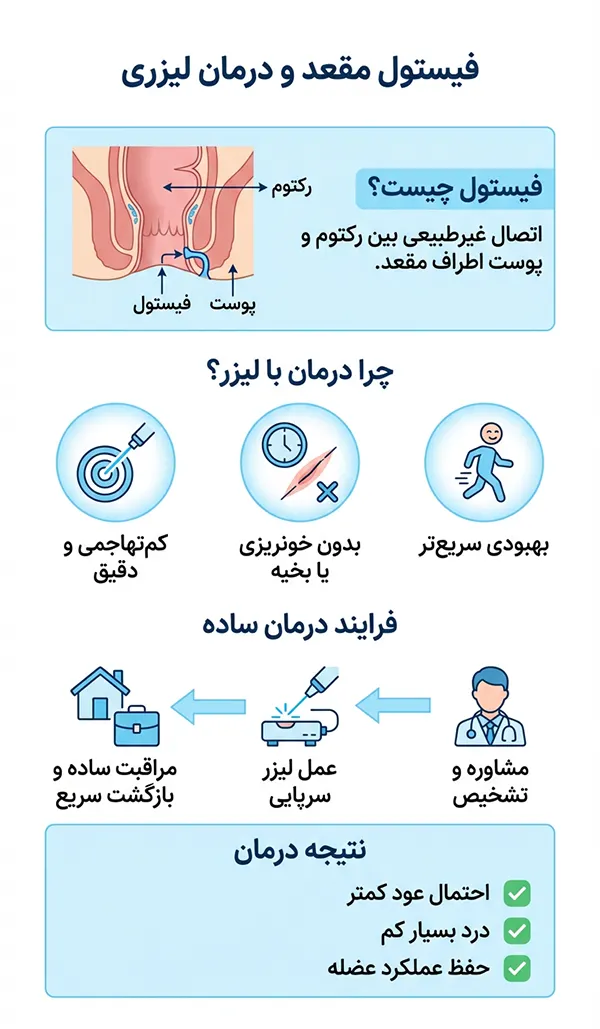

منظور از فیستول مجرا یا سوراخ حاوی عفونت است که بین هر بافت طبیعی در بدن ممکن است رخ دهد. یکی از نواحی که احتمال بروز فیستول در آن زیاد است ناحیه مقعد است. درمان های متفاوتی برای فیستول مقعدی وجود دارد یکی از درمان های که این روزا بسیار مورد توجه عموم قرار گرفته است درمان فیستول مقعدی با لیزر است. این شیوه درمانی به دلیل عوارض پایین و عملکرد عالی مورد استقبال بیماران قرار گرفته است. در ادامه اطلاعات بیشتری در مورد لیزر فیستول در اختیار شما قرار می دهیم.

در درمان فیستول با لیزر نیازی به بیهوشی نیست و با بی حسی ناحیه مقعد فیستول را لیزر می کنند. طی عمل لیزر فیستول ابتدا مجرای فیستول را با مواد مخصوص ضد عفونی و تمیز می کنند بعد لیزر را که از یک سری و یک فیبر نوری متشکل شده است از داخل بافت فیستول به آرامی عبور م دهند. لیزر به آرامی بافت مجرای فیستول را التیام می بخشد و از بروز عفونت در آینده پیشگیری می کند.

طی یک جلسه لیزر به صورت سرپایی حدود نیم ساعت می تواند انواع فیستول مقعدی را درمان کرد. درمان فیستول با لیزر با کمترین درد و خونریزی انجام می شود و احتمال عود فیستول در آینده نسبت به روش های سنتی بسیار پایین است.

لیزر از نور بدون خطر مادون قرمز برای التیام بافت و بسته شدن مجرای فیستول استفاده می کند. پس نگران لیزر نباشید چرا که این لیزر بی خطر بوده و در درمان فیستول با موفقیت عمل می کند.

مزایای درمان فیستول با لیزر

- سرپایی بودن یعنی بدون نیاز به بستری

- بدون نیاز به بیهوشی عمومی فقط با بی حسی موضعی

- عدم نیاز به پانسمان و تعویض آن

- کمترین مدت دوران نقاهت نسبت به سایر روش های درمان فیستول

- درمانی قطعی که احتمال عود فیستول نزدیک صفر است

- برخلاف روش های جراحی که جای زخم بزرگ در ناحیه مقعد باقی می ماند در این شیوه وجود جای زخم کم است

- هزینه کمتری نسبت به جراحی دارد.

- احتمال آسیب به عضله اسفنکتر مقعد (بی اختیاری مدفوع) بسیار پایین است.

- پروسه لیزر فیستول حدود نیم ساعت طول می کشد.

- به دلیل استفاده از لیزر احتمال انتقال ویروس های خطرناک پایین می آید.